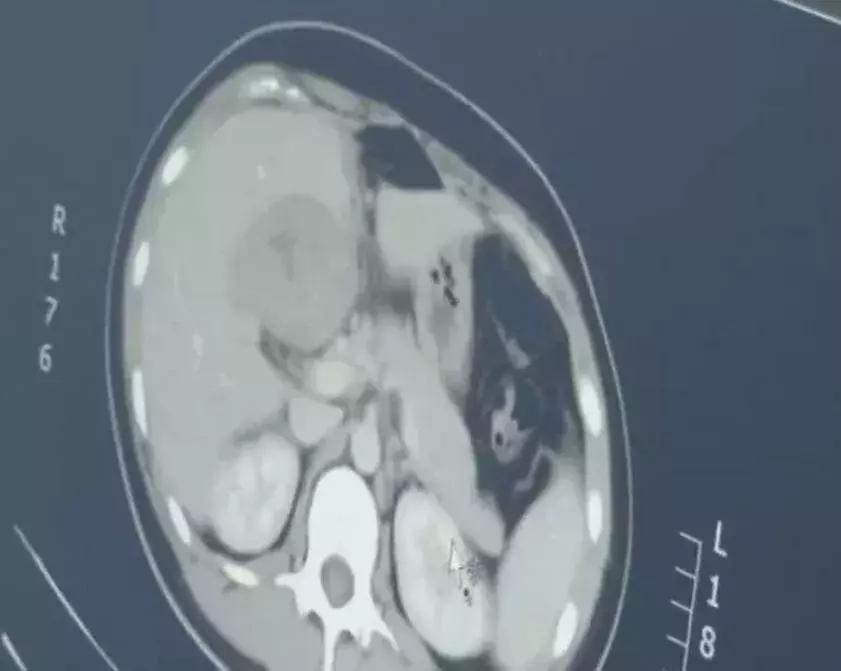

于是给尤女士做了CT,

最后竟然在肝脏部位,

找到了胚胎……

连见多识广的医生都感叹:

这是一个罕见的宫外孕病例!

据介绍,宫外孕常见于输卵管附近,胚胎跑到肝脏部位极为罕见,很容易引发大出血,危及生命。